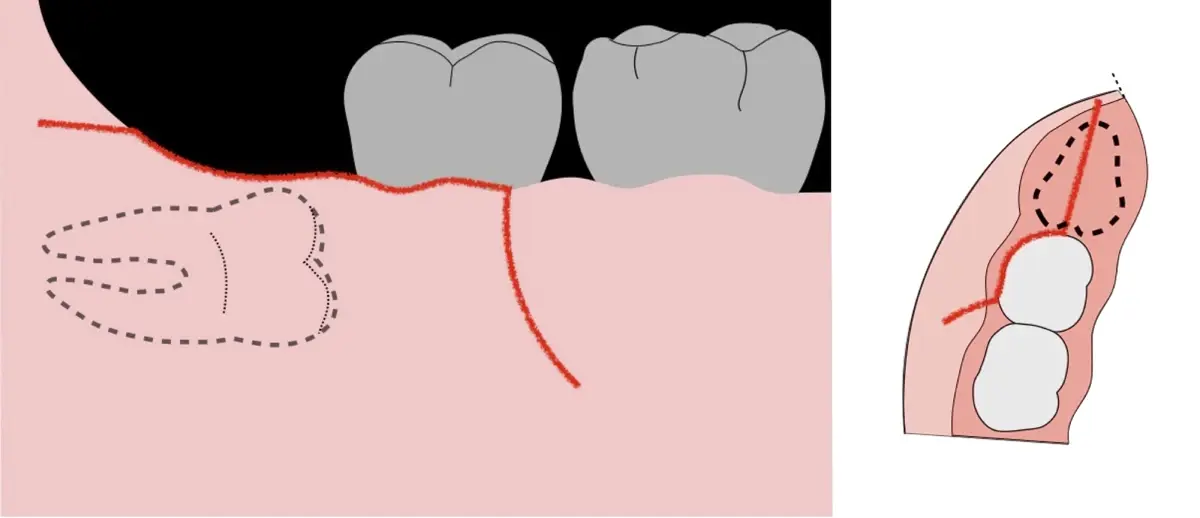

El procedimiento se inicia colocando anestesia troncular para bloqueo del nervio dentario inferior y sus ramas. Luego, se establecerá el diseño de acceso según la disposición de la molar a extraer. Para fines didácticos, se explicará cómo se realizaría la extracción de la molar de la Figura 1: se realiza una incisión horizontal a nivel de la zona retromolar hasta llegar a distal de la segunda molar, continuándose con una incisión intrasurcular hasta mesial de la segunda molar, finalizando con una incisión vertical a espesor total hasta llegar a la línea mucogingival (Figura 2).

Figura 2. Diseño de incisión para el acceso a la tercera molar.